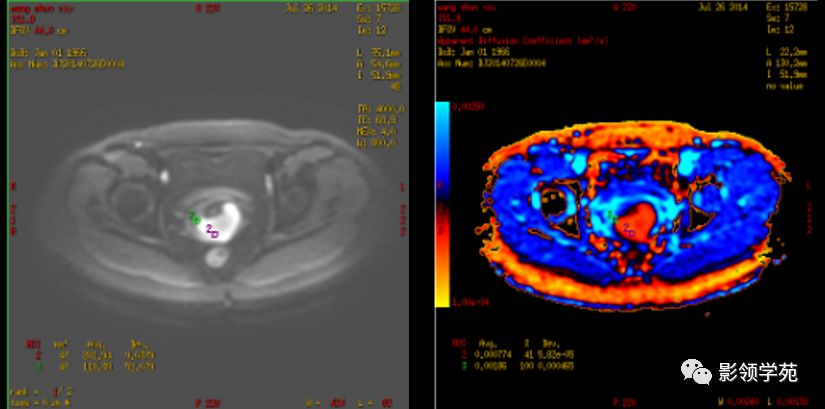

磁共振扩散加权成像,DWI

DWI是目前唯一能在活体观察组织水分子微观运动的无创性影像学方法,可以检测出与组织含水量变化相关的形态学和生理学早期改变,并以表观扩散系数(ADC)值来量化表示。

DWI在宫颈癌中的应用

DWI:局限性高信号,癌组织ADC值<癌旁组织<小于正常宫颈组织